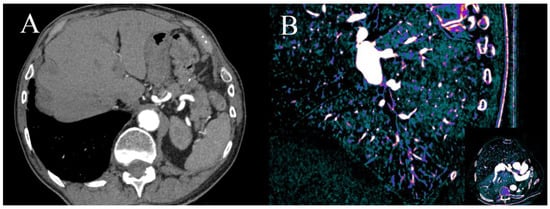

Figure 5.

MPR MIP image of true unenhanced image (A) and water (iodine) map (B) showing calcifications in the LCx. The volume of calculated calcifications was 85 mL and 88 mL, respectively. Similar results, showing high correlation between calcium volume calculated from TUN and VUIs, were reported by [24].